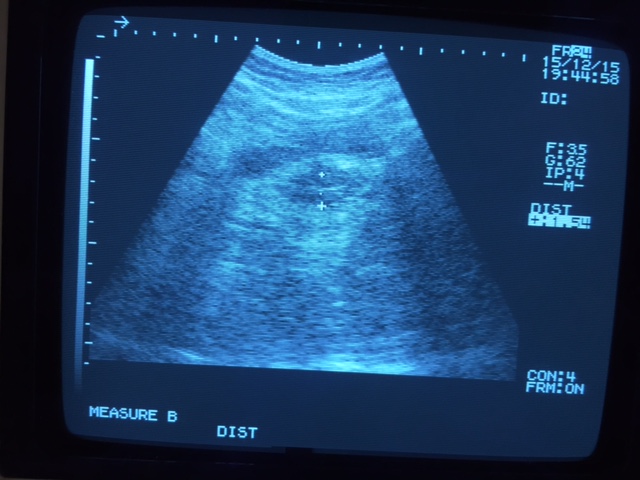

当院にはエコーがある。2ヶ月経過してそれを見たところ、おそらく7ミリ台にまで回復していたので、急遽婦人科へ行って頂いた。(医師の経膣エコーと、私たちが使う経腹エコーでは、見え方がまったく異なるので、その計測には諸種条件を考慮した換算が必要である)

医師は当分休むように言っておられたが、内診すると8ミリ近くまで厚くなっていたので、翌月から移植準備に入ろうということになった。